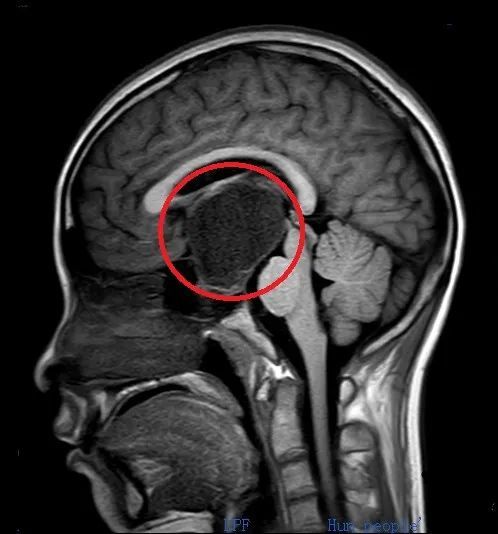

术前头部CT和磁共振检查显示:鞍区肿瘤(红圈内)比乒乓球还大,压迫周围重要的神经和血管。

入院后进一步检查发现,肿瘤约为4.5×4.4×4.6cm,比乒乓球还大,周围遍布颈内动脉、视神经、三脑室底、海绵窦、垂体、垂体柄等重要的神经和血管。

医生告诉小雯和家属,由于肿瘤压迫视神经,因此导致她视力减退;还压迫垂体,导致其内分泌紊乱、月经失调,并形成颅高压。如不尽快手术,病情继续进展可能危及生命。